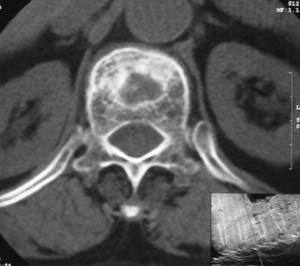

患者,女,72岁,胸背部疼痛3月余,无明显外伤史。曾应用局部封闭、非甾体类止痛药治疗效果不明显,近来疼痛缓解频感背困,平卧缓解,近日行ct检查发现胸12椎体病变,烦请同道发表意见,诊断什么?有何治疗经验!谢谢!!!

标绘图示:第十二胸椎级第一腰椎椎体楔形改变。ct扫描示:第十二胸椎椎体骨质结构紊乱,并可见一囊状低密度影,边缘可见硬化,椎体皮质完整。

考虑:第十二胸椎陈旧性骨折、许莫氏结节。